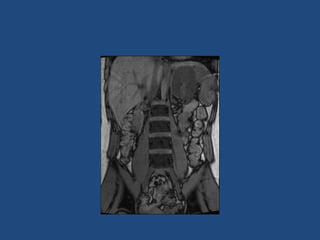

• CT better at eliminating malignancy

(dedicated CT looking at Hounsfield units (HU)

and washout characteristics)

– <10HU = benign (sens 71%, spec 100%)

• MRI may characterise phaeos better

• FDG-PET good for phaeos and cancer

• FNA – consider if cancer history and >10HU on CT

after exclusion of phaeo

Imaging

•

>6cm high suspicion of malignancy

3-6cm repeat imaging in 3-6M

Delayed washout on contrast is suggestive

most are often inhomogeneous, irregular

margins

• Look for invasion of IVC

• Always do CAP and consider bone scan and

pet if in doubt

• Don’t ever biopsy (tumour spill)